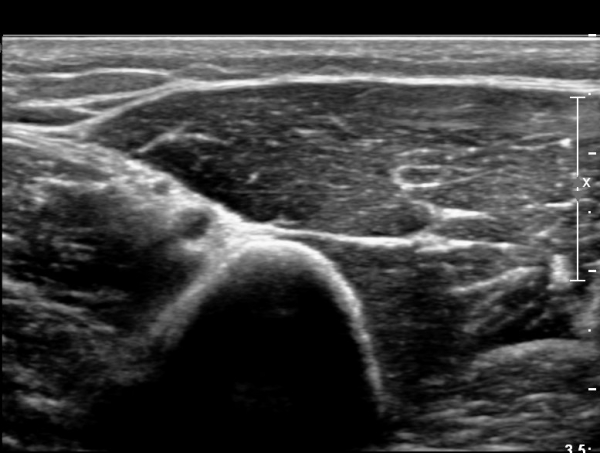

¿ä°ñ °í¶û¿¡¼ ¿ä°ñ½Å°æ Ⱦ´Ü¸é°Ë»ç»ó ¿ä°ñ½Å°æÀÇ °æ¹ÌÇÑ Àú¿¡ÄÚ ºÎÁ¾ÀÌ °üÂûµÈ´Ù(»çÁø 2).

ŽÃËÀÚ¸¦ Á¶±Ý ¸»´ÜÀ¸·Î À̵¿ÇÏ´Ï ¿ä°ñ½Å°æ Àú¿¡ÄÚ ºÎÁ¾ÀÌ ´õ¿í ¶Ñ·ÈÇѵ¥(»çÁø 2),